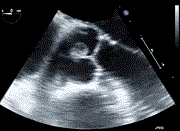

Rare case of papillary fibroelastoma resection with concomitant cox-maze IV procedure

Zamaan Hooda and others

Journal of Surgical Case Reports, Volume 2022, Issue 8, August 2022, rjac371, https://doi.org/10.1093/jscr/rjac371

Mitral valve replacement with papillary muscle tugging approximation in a patient with severely impaired left ventricular function 14Â years after initial mitral valve repair

Tomoki Nakatsu and others

Journal of Surgical Case Reports, Volume 2022, Issue 8, August 2022, rjac339, https://doi.org/10.1093/jscr/rjac339